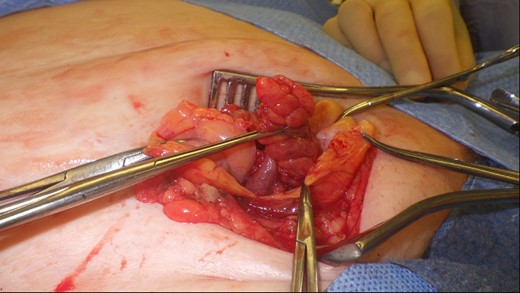

This 82-year-old lady presented with a sudden painful right sided groin swelling not previously noticed. She had no features of obstruction and was opening her bowels and not vomiting. Her medical background included left sided femoral hernia repair in 2005, coronary artery bypass graft and bilateral total knee replacements. On examination her abdomen was soft with the presence of a tender, irreducible swelling in the right groin, inferolateral to the pubic tubercle. She had good bowel sounds and there was stool present in the rectum on PR examination. A full set of blood tests demonstrated no abnormality. A CT abdomen and pelvis demonstrated an incarcerated right sided femoral hernia containing an 8 mm long inflamed appendix with a small amount of localized free fluid and inflammation indicative of De Garengeot’s hernia with underlying acute appendicitis (Fig. 1). The hernia sac diameter measured 2 mm on CT scan. She was taken to theatre for an open Lockwood repair of her femoral hernia and an appendicectomy. Following an initial Lockwood incision over the lump, dissection was performed down to the hernia sac also exposing the inguinal ligament (Fig. 2). The tightness of the femoral ring made mobilization of the appendix difficult. By partially incising the inguinal ligament superior to the femoral ring, the appendix was freed, and on inspection showed inflammation particularly towards the tip (Fig. 3). The caecum was then reduced and the inguinal ligament was repaired with non-absorbable suture. The femoral hernia was then repaired with a small funnel of ultrapro mesh. Appendicectomy was then performed in the usual fashion via the Lockwood incision leaving a slightly longer stump than usual (Fig. 4).

De Garengeot’s hernia – femoral hernia sac containing the vermiform appendix.